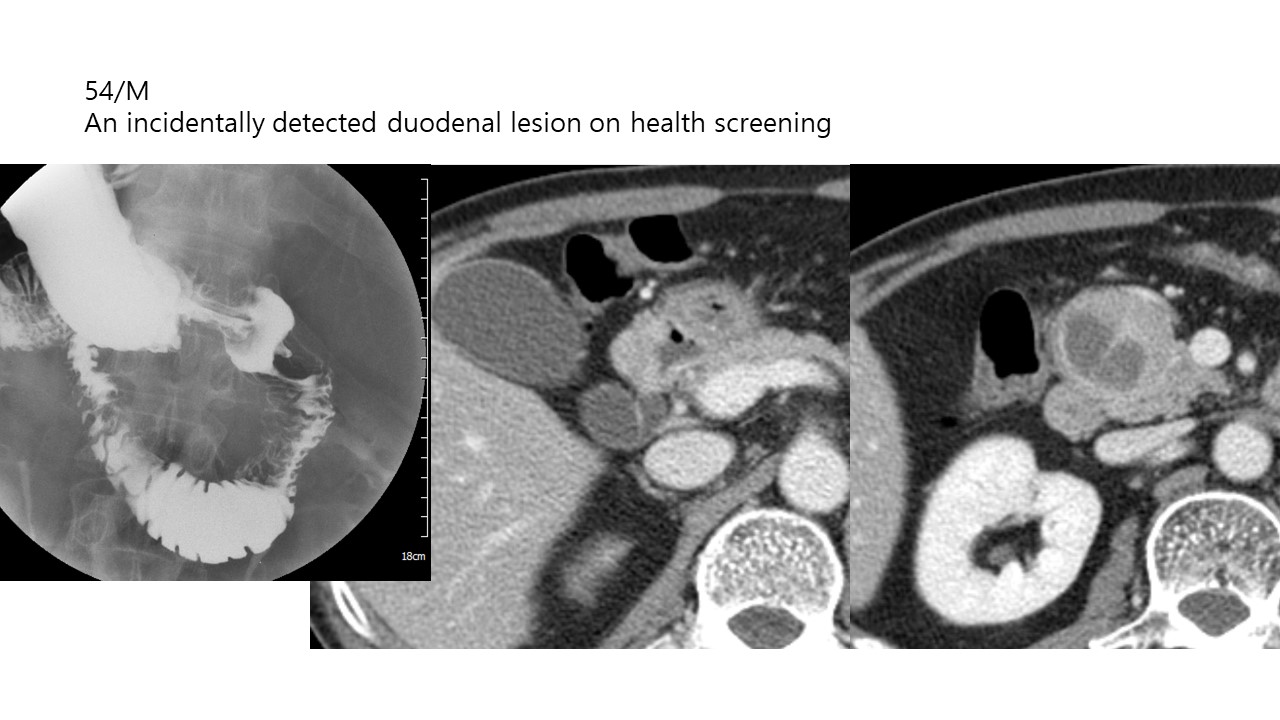

M / 54

54/M An incidentally detected duodenal ...

ABDOMEN

So Hyun Park

Seoul National ...

574

2026-02-18